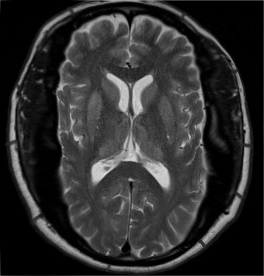

对阶段4的SCP-7694-1个体的脑部核磁共振结果,显示出肿胀的的颅骨和瘘管。

对阶段3个体的核磁共振扫描表明在颅内腔和鼻腔间形成了瘘管。这导致脑脊液泄漏入鼻腔和食管,导致喷嚏和呕吐物具有极高感染性。